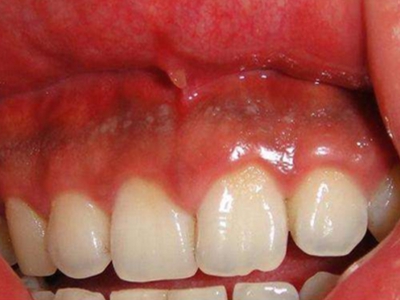

牙龈癌多源于牙间乳头及龈缘区,溃疡呈表浅、淡红,以后可出现增生。由于黏骨膜与牙槽突附着甚紧,较易早期侵犯牙槽突骨膜及骨质,进而出现牙松动,并可发生脱落。X线片可出现恶性肿瘤的破坏特征虫蚀状不规则吸收。

牙龈癌常发生继发感染,肿瘤伴以坏死组织,触之易出血。体积过大时可出现面部肿胀,浸润皮肤。